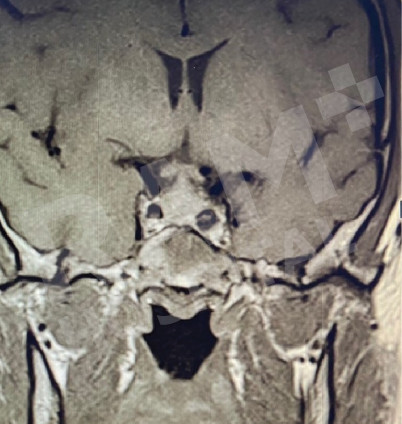

磁共振成像(MRI)可清晰、细致地显示垂体的异常病变,精准定位垂体腺瘤的位置;结合静脉造影增强检查,还能明确腺瘤的具体位置与病变性质,同时清晰呈现脑部周边组织及鼻窦的情况。这一项检查结果可为制定诊疗方案、随访评估垂体腺瘤的治疗效果,乃至规划手术方案提供明确、可靠的依据。

| 术前 | 术后 |